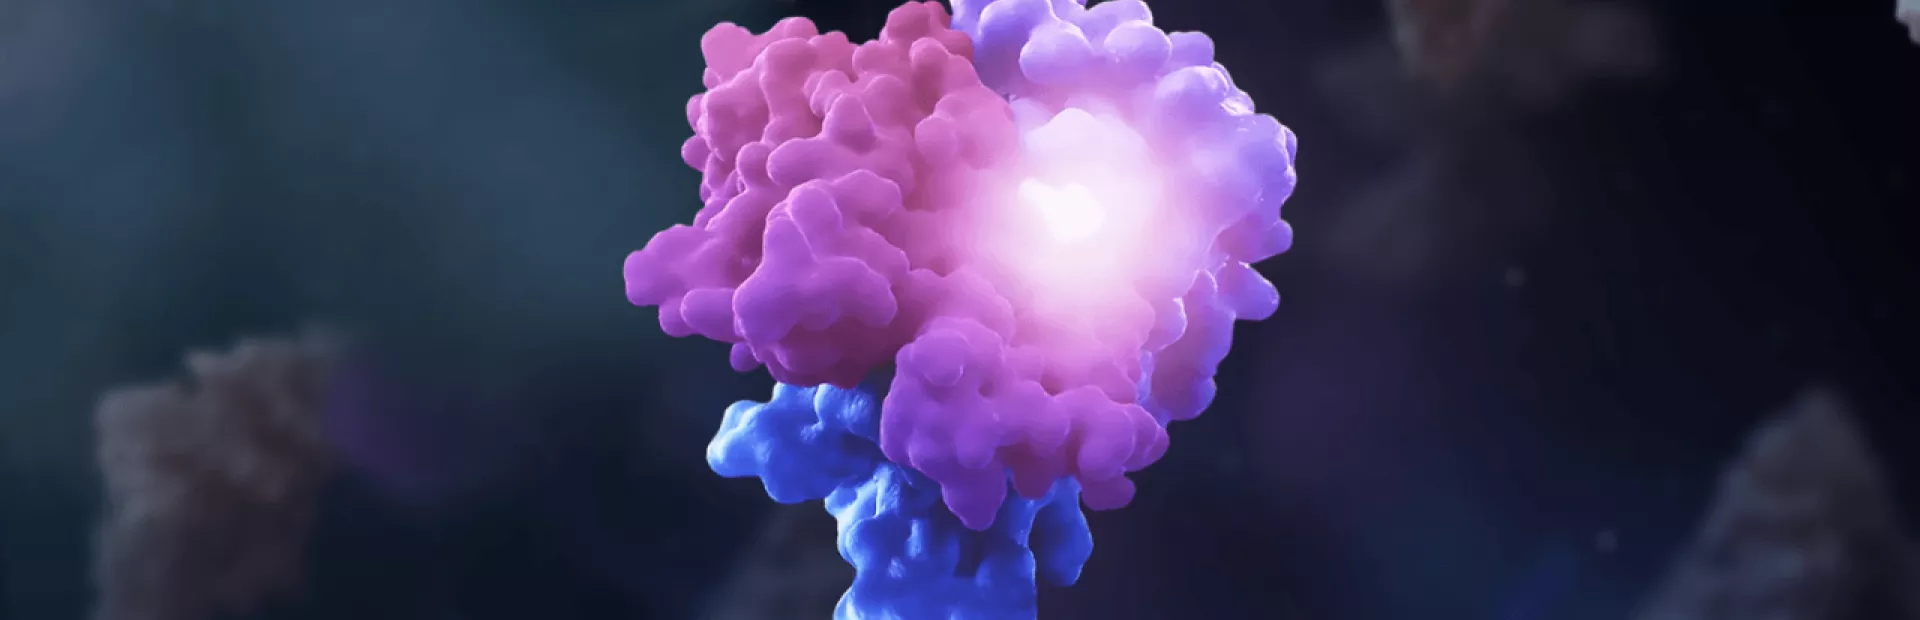

細胞の中では、タンパク質は常に互いにぶつかり合っています。多くの細胞活動は、タンパク質同士の相互作用の結果として起こっています。分子接着剤は、タンパク質を自身に、もしくは別のタンパク質にくっつける仲人役を果たしています。

医薬品としての分子接着剤の凄い所は、通常は相互作用しないタンパク質同士を結合させることです。ほとんどの生物活性はタンパク質間の相互作用によって引き起こされるため、分子接着剤により疾患と闘う生物学への新たな扉が開かれます。

たとえば、分子接着剤を使って疾患を引き起こすタンパク質に「ゴミ」というタグを付けることで、細胞がそのタンパク質を排除するよう誘導することができます。また、疾患に関連するタンパク質を分子接着剤自身に結合させて機能を停止させ、疾患に関連するプロセスを遮断させる可能性も考えられます。